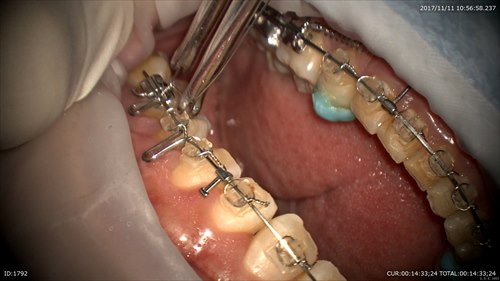

1ケース目:矯正治療

矯正治療で空いたスペースを埋める工程に入った所で前歯の角度を入れているところです。

オーダーメイドでこの工程は作っていきます。

左上の抜歯したスペースをタイバックで埋めていきます。

今日は少し違和感でますよー。